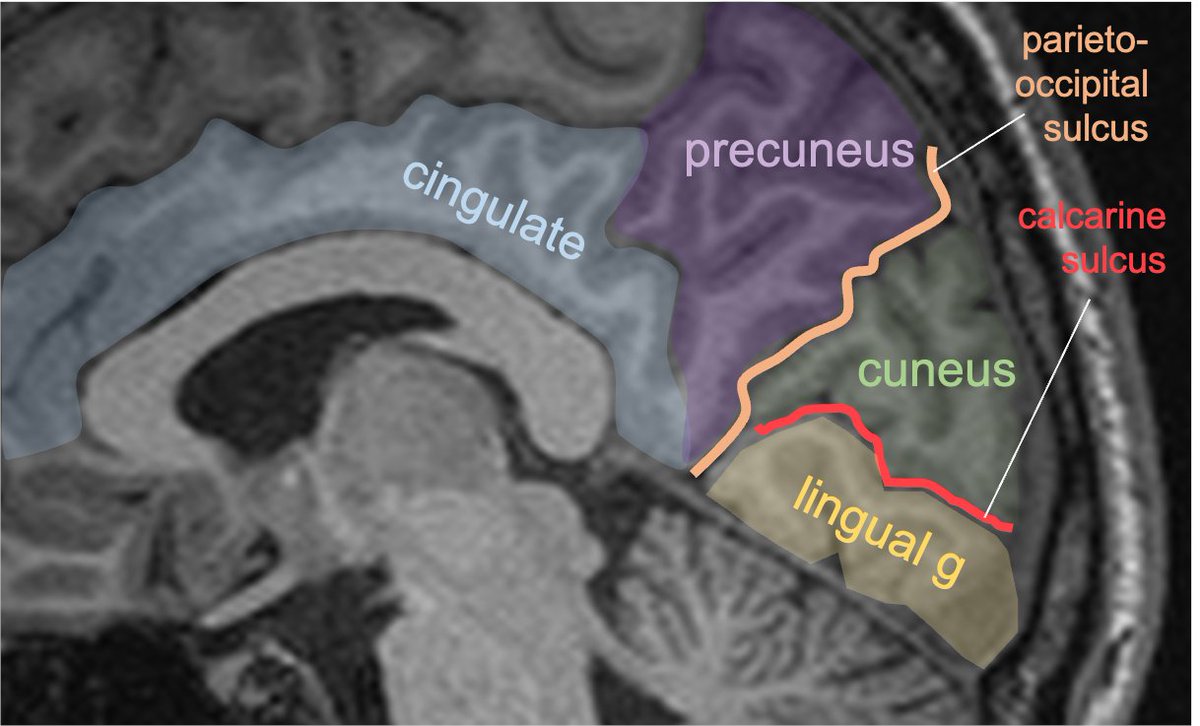

Gyral anatomy of the medial brain surface: calcarine sulcus divides the cuneus from lingual gyrus at the med occ lobe. The lingual g continues anteriorly along the med/ inferior temporal lobe. The cingulate g wraps sup & posterior to corpus callosum along the medial brain.

The lingual gyrus is involved in holistic visual and word processing, encoding visual memories, imagery, and dreaming. The ganglioglioma in the shown case is centered in the lingual gyrus.